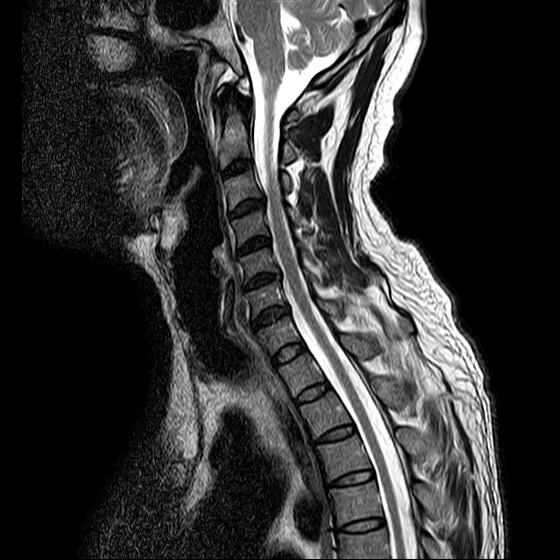

ũ Ͻ е鲲 ǰ ϴ. ڸ 4°Դϴ. ũ ϴ. (ڸǥغ ǥغ ) @ : 2014. 2.15 ĺ Ȳġ Ͽ. -> κ ǿ ġϿ պ ϱ. @ 2014. 3. 27 к mri, ct ũ ϰ ؾ Ѵٰ. @ ũ ġ ͳ Ͽ ڸǥغ Ͽ. ϱ : .(ó ) 2014. 4. 12() --- <1°> : Ͽ ȸ . 㳻 : (ڱ , Ӹ е ħ ˷. ¿ . ų ɰų Ҷ ̰ų ڼ . 201.4. 4. 13() ---<2°> 1. ħ Ͼ ¿ ȭ . 2. ħ е ħ . 3. ü ƮĪ ˷. ڼ ˷ֽŴ ϸ ڼ ùٸ ϸ Ÿ ˷ֽ Ư ƮĪ ϸ Ѱ پ 2014. 4. 14() ---<3°> : : پ(ó ߴ.) 㳻 : 1. ħ Ͼ ¿ ȭ . 2. ũ ˷ . 2014. 4. 14() ---<4°> : پ(ó .) 㳻 : 1. 繫ǿ ũ ٽ 2. ũ ˷ ϸ ڼ ϸ ȸ ̷ ɴ 2~3 ϸ ȸȴٰ Ͻô ū 븦 Ͽ ȸϵ ϰڽϴ. ȸ Ź帳ϴ. ũ mri Ȳ Դϴ. Ű 179 86 51 ()ijħ ڸǥغ ǥغ ˰Ե ͳ ˻ڷ õ ()ijħ ڸǥغ ǥغ ϱ ȣϽ 6C.ڸ 6C.ھ Ḳ 7C.Ȳġ 1T.Ȳġ 1T. κ ()ũ( ߰Ż) ڸ(߹) ũ(߰) Ը ũ(߰Ż)ġ, ()ijħ ڸǥغ ǥغ ϰ ߴ ġ 1. : 2014. 2.15 2. ġ : Ʒ(ô߿ ) , ȱ 3. **뺴 : ˾. Ƽ (ũ ) 4. ó : ڰ, 3 Ⱓ mypol()ó. ȭ. 3 5. ü ġ . |